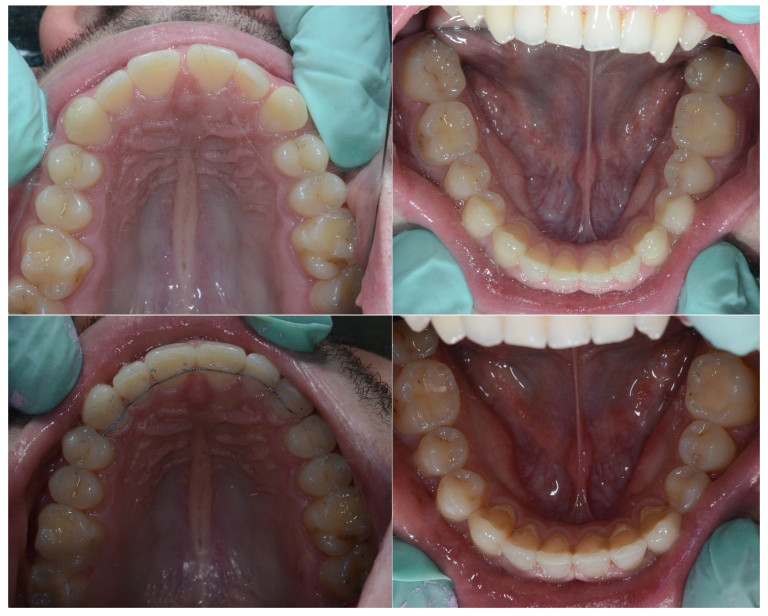

U galeriji slika su prikazani klinički slučajevi ovakvih odraslih pacijenta bilo da se radi samo o ortodontskoj terapiji ili predprotetskoj ortodonciji.

Kompresija –fiksni aparat bez ekstrakcije zuba

Slučaj 1

Slučaj 2

Slučaj 3

Slučaj 4